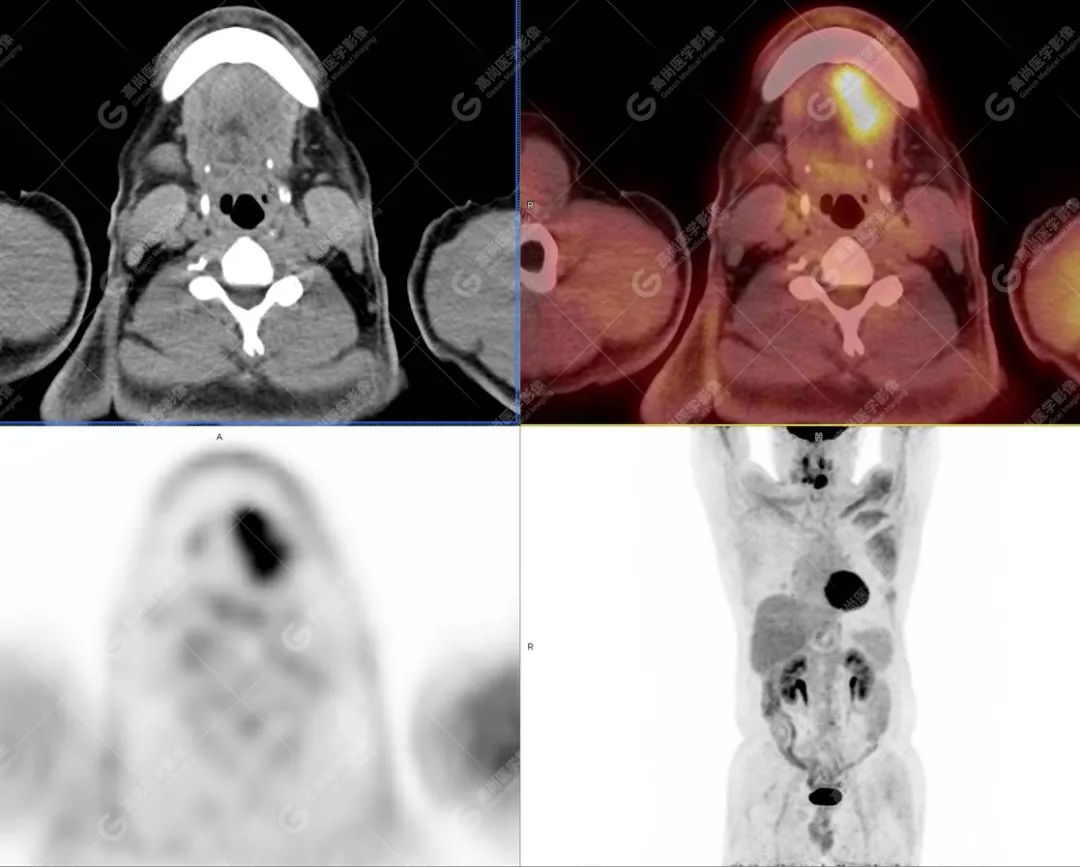

PET/CT影像图

图3

影像诊断: 1.舌体部左右侧软组织明显增厚,密度稍低,左侧为著,代谢异常增高, 考虑为舌癌,并口底受侵, 建议穿刺病理学检查明确。

2.双肺多发大小不等实性结节,部分代谢轻度增高, 考虑为转移瘤。

术后 病理: 口底癌; 考虑为口底癌侵犯舌神经致舌部麻木感。